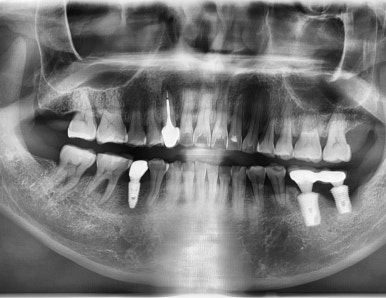

- 앞니 브릿지가 다 빠져서 흔들거려 발치해야 하고

어금니는 다른데서 임플란트가 찢어져 실패하여 뼈에 묻혀져 있던 케이스

임플란트 수술 전

처음 오셨을 때 기존에 앞니 다른데서 하신 브릿지는

속치아가 다 썩어 분리되어 흔들리는 상태였고

어금니쪽 임플란트는 찢어져서 임플란트 머리를 올리지 못한 상태였습니다.